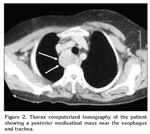

The patient was referred to the thoracic surgery department for further evaluation of mediastinal mass causing hypercalcemia. Her serum calcium and phosphorus levels were 13.2 mg/dL and 2.5 mg/dL, respectively. Intact parathormone level was 642 pg/mL (normal range 8 to 97 pg/dL). A technetium-99m pertechnetate methoxy-isobutyl-isonitrite (Tc-99 m MIBI) scan was revealed a mass in the mediastinum. Computed tomography (CT) revealed a heterogeneous hypodense right paratracheal mass compressing esophagus (Figure 2). A fine needle aspiration under CT guidance did not yield tumor cells. The thyroid gland appeared normal and no other pathologic lesion was found on USG and scintigraphy.